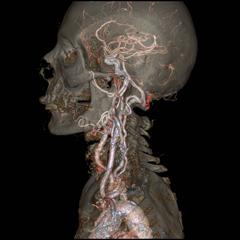

A new generation of CT scanners is being readied to produce angiograms, captured at high speeds and paradoxically low radiation dose, that might allow the more accurate planning and effective implantation of stents, as well as repair heart valves; for example, transcatheter aortic valve implantations. Such exams are possible now only with Toshiba’s pathfinding Aquilion One, but soon competitors from Siemens and GE, shown as works in progress at this year’s RSNA meeting, will enter the market.

The GE Revolution CT can capture a human heart in a single beat free from motion artifact. At the show, the company framed the 510(k)-pending system as an “all-in-one” scanner, offering coverage, spatial and temporal resolution that can handle a comprehensive range of radiological applications, while serving as a platform for new applications.

Siemens billed its Somatom Force as the next generation in dual-source CT. Successor to the Somatom Definition Flash, the company’s previous top-tier CT, Force features two generators that — like the generators on its predecessor — fires X-rays independently at variable energies. Force is so fast, however, that it can image the adult chest in a second, eliminating the need to breathhold, and freeze a human heart pumping at 90 beats per minute by merging the two imaging chains to create a 50 cm (nearly 19.7-inch) field of view. Alternatively the two imaging chains, like those on the Flash, can be tuned to separate energies to differentiate among tissues or materials, as in visualizing iodinated contrast as it flows through the coronaries or accumulates in varying amounts in benign versus malignant masses, such as those in the kidney.